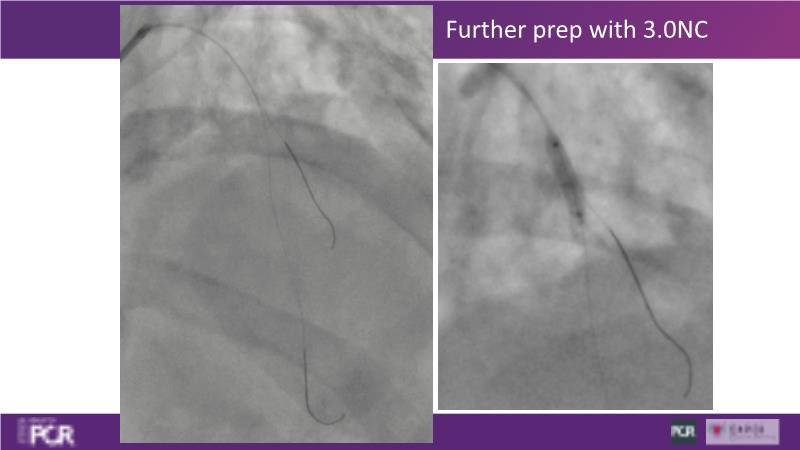

Through the study of two cases, this session examines the need for stenting bifurcation lesions and the role of DEB technology in avoiding stent-related complications in long diffuse disease. It emphasizes the benefits of SELUTION SLR balloons for de novo lesions, discussing how sustained limus release technology can broaden DEB indications and reduce metal usage, understanding the limitations of DES and the emerging role of DEB with sustained limus release, and learning how to identify dissections that can be left unstented.